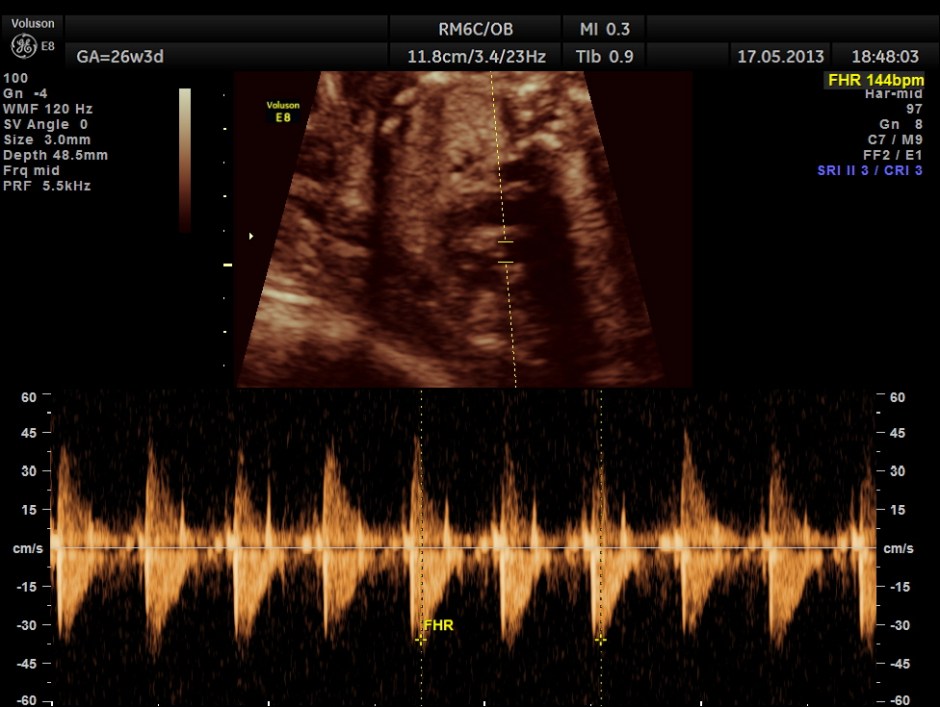

The following images show the sections of the heart.

This fetus did not show any oro-facial clefts ; heart and spine appeared normal.